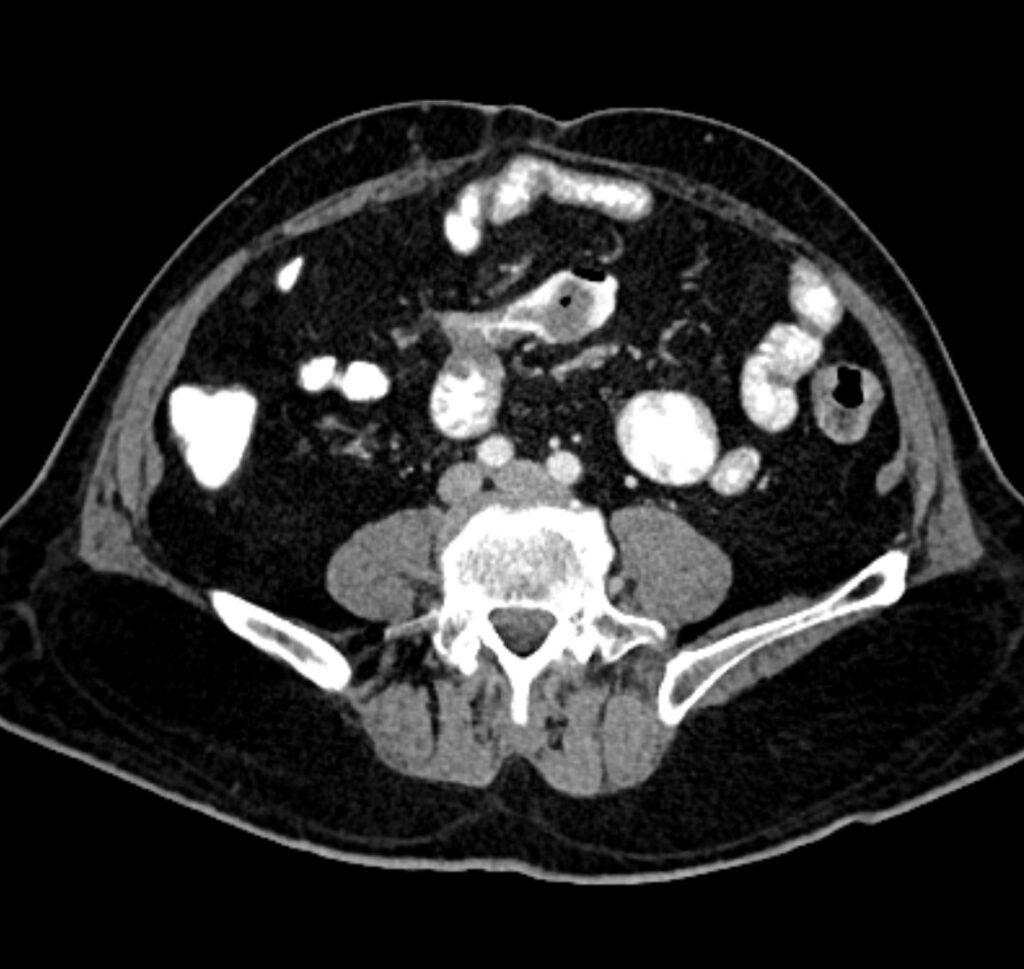

*72-year-old male with abdominal pain and vomiting.

Answer: Small bowel mesentery internal hernia

CT images revealed the dilated loops, mesenteric edema, and beak-like point of obstruction

There are two types transmesenteric and intramesenteric small bowel internal hernia.